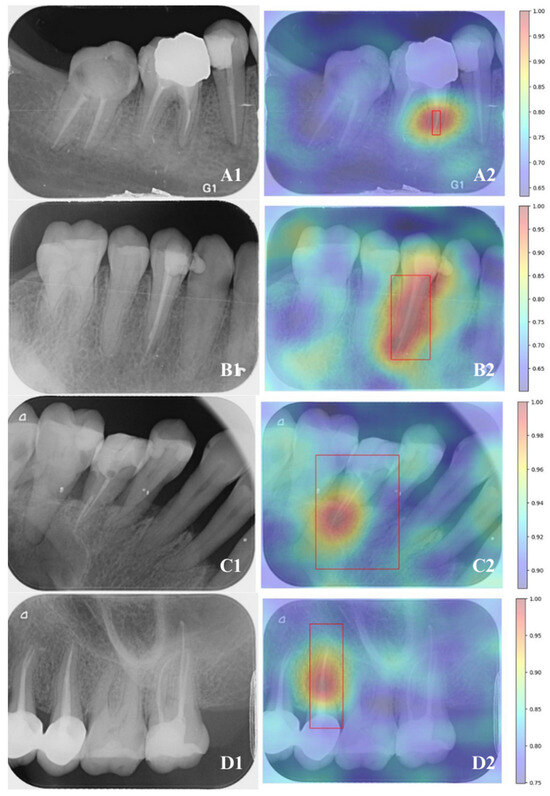

| Accuracy | IoU (Intersection Over Union) | mAP50 | Interference Time | |

|---|---|---|---|---|

| YOLO v8 | 0.973975 | 1.00 | 0.989 | 14.6 ms |

| Mask-R-CNN | 0.982075 | 0.99 | 0.950 | 88.7 ms |

| p | 0.571 | 0.146 | 0.020 |

| Endodontist A | Endodontist B | Mask-R-CNN | YOLOv8 | A-B (p) | A- Mask-R-CNN (p) | A- YOLOv8 (p) | B- Mask-R-CNN (p) | B- YOLOv8 (p) | Mask-R-CNN-YOLOv8 (p) | |

|---|---|---|---|---|---|---|---|---|---|---|

| BG F1 Score | N/A | N/A | 0.9893 | N/A | --- | --- | --- | --- | --- | --- |

| FEI F1 Score | 0.9947 | 0.9947 | 0.9890 | 1.0000 | 1.000 | 0.640 | 0.447 | 0.640 | 0.447 | 0.272 |

| RCT F1 Score | 0.9944 | 0.9944 | 1.0000 | 0.9964 | 1.000 | 0.447 | 0.832 | 0.447 | 0.832 | 0.542 |

| BG- FEI (p) | --- | --- | 0.971 | --- | ||||||

| BG- RCT (p) | --- | --- | 0.064 | --- | ||||||

| FEI- RCT (p) | 0.967 | 0.967 | 0.126 | 0.382 |